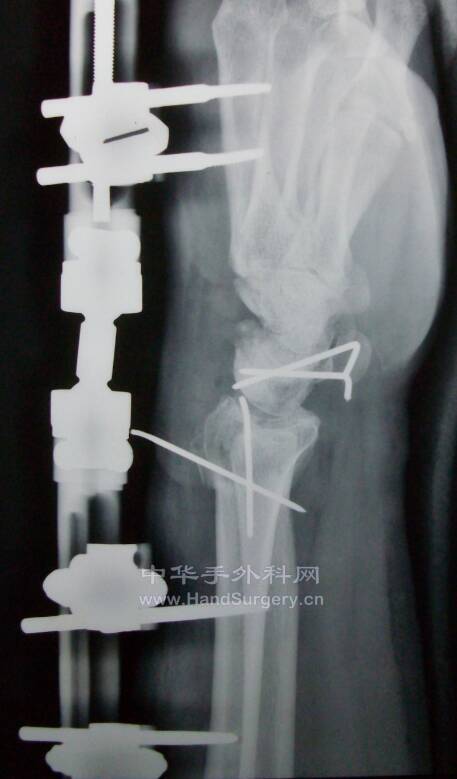

桡骨远端骨折,远端粉碎或太短,不能接受钢板远端钉排

克氏针+外固定支架是绝佳选择

这里就是其中一个典型病例

桡骨远端骨折C3型合并舟骨骨折

有限切开,外固定架的持续牵引,可以利用软组织夹板作用,维持粉碎骨块的复位